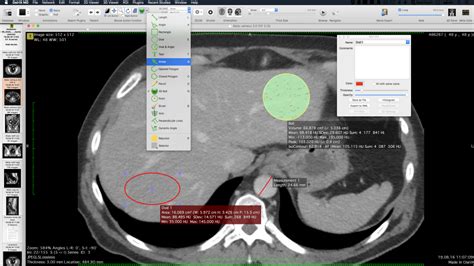

Now, let’s really get into the nitty-gritty of OsiriX MD and what makes it such a powerhouse for image processing and analysis. Guys, this is where the software truly shines and justifies its reputation. Beyond just viewing DICOM files, OsiriX MD offers a suite of advanced tools that allow for in-depth investigation of medical images. One of the standout features is its segmentation capability . This allows you to isolate specific tissues or structures within an image, which is critical for things like measuring tumor volume or analyzing blood flow. You can manually segment, or use semi-automatic tools, and the results are often incredibly precise. This level of detail is absolutely vital for tracking disease progression or planning complex treatments. Imagine being able to precisely outline a lesion, track its growth over time with quantitative measurements, and then present that data clearly. That’s the kind of power OsiriX MD puts in your hands. Another area where OsiriX MD excels is in its measurement tools . It’s not just about simple distances; you can perform sophisticated quantitative analysis, including area, volume, angle, and even Hounsfield unit (HU) measurements. This is super important for objective assessment and reporting. For instance, you can measure the density of a particular tissue or the volume of an organ with high accuracy. These quantitative metrics are often required for clinical trials, research studies, and precise medical reporting, and OsiriX MD delivers them reliably. The software also supports a wide range of image processing filters that can enhance image quality or highlight specific features. You can apply noise reduction filters, sharpen edges, or adjust contrast and brightness extensively. This is crucial for optimizing images for diagnosis, especially when dealing with subtle findings or images acquired under less-than-ideal conditions. Think about being able to remove noise from an MRI to make fine details pop, or enhance the visibility of blood vessels in a CT angiogram. The flexibility here is immense. Furthermore, OsiriX MD integrates seamlessly with plugins and extensions , allowing you to extend its functionality even further. Whether you need specialized algorithms for cardiac analysis, neuroimaging, or radiation therapy planning, there’s likely a plugin available or you can even develop your own if you have the expertise. This extensibility means OsiriX MD can grow with your needs and adapt to new technologies and research advancements. It’s not a static tool; it’s a dynamic platform that can evolve. For researchers and clinicians who push the boundaries of medical imaging, this adaptability is invaluable. The ability to perform complex calculations, generate detailed reports with integrated measurements and annotations, and export data in various formats further cements OsiriX MD’s position as a comprehensive analytical solution. It’s designed to streamline complex workflows, reduce manual errors, and ultimately improve patient care through more accurate and efficient image analysis. The investment in learning these advanced features definitely pays off in terms of diagnostic confidence and research output.